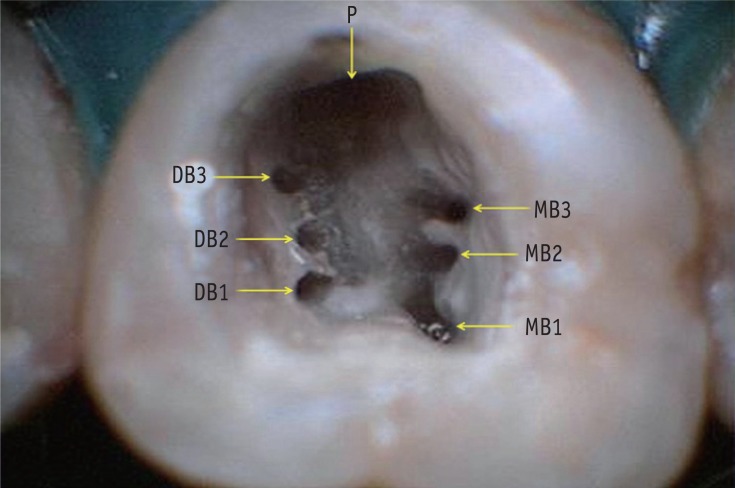

Access chamber showing seven root canal orifices of tooth 16. MB, mesiobuccal; DB, distobuccal; P, palatal.

Radiographic evaluation of the involved teeth revealed three completely formed roots with no indication of any variation in the root canal anatomy (Figure 1a). The teeth were anesthetized using 1.8 mL 2% lidocaine with 1:200,000 epinephrine (Xylocaine, AstraZeneca Pharma Ind Ltd, Bangalore, India). The proximal surfaces of both the teeth were restored with composite resin (P60, 3M ESPE Dental Products, St Paul, MN, USA) after caries excavation to enable optimal isolation. Following rubber dam isolation, an endodontic access cavity was prepared on tooth 16 and 17. On inspection with a DG-16 endodontic explorer (Hu-Friedy, Chicago, IL, USA) under an operating microscope (Roslane Meditech, Haryana, India), the pulp chamber floor revealed two canal openings in the mesiobuccal root (MB1 and MB2), and one in the distobuccal (DB1) and palatal root on teeth 16 and 17. Anticipating the presence of extra canals, further exploration of the pulpal floor was carried out with a DG-16 endodontic explorer (Hu-Friedy) on tooth 16 on the line connecting the orifices of the buccal and palatal canal along the floor-wall junction. A "catch" just palatal to the orifice of the MB2 canal unveiled the third canal (MB3) in the mesiobuccal root. In addition, two sticky points were also detected on the line connecting the distobuccal and palatal canal orifices which led to the finding of two additional canals in the distobuccal root (DB2 and DB3, Figure 2). Inspection of the pulpal floor on tooth 17 was done for search of other orifices that were absent.